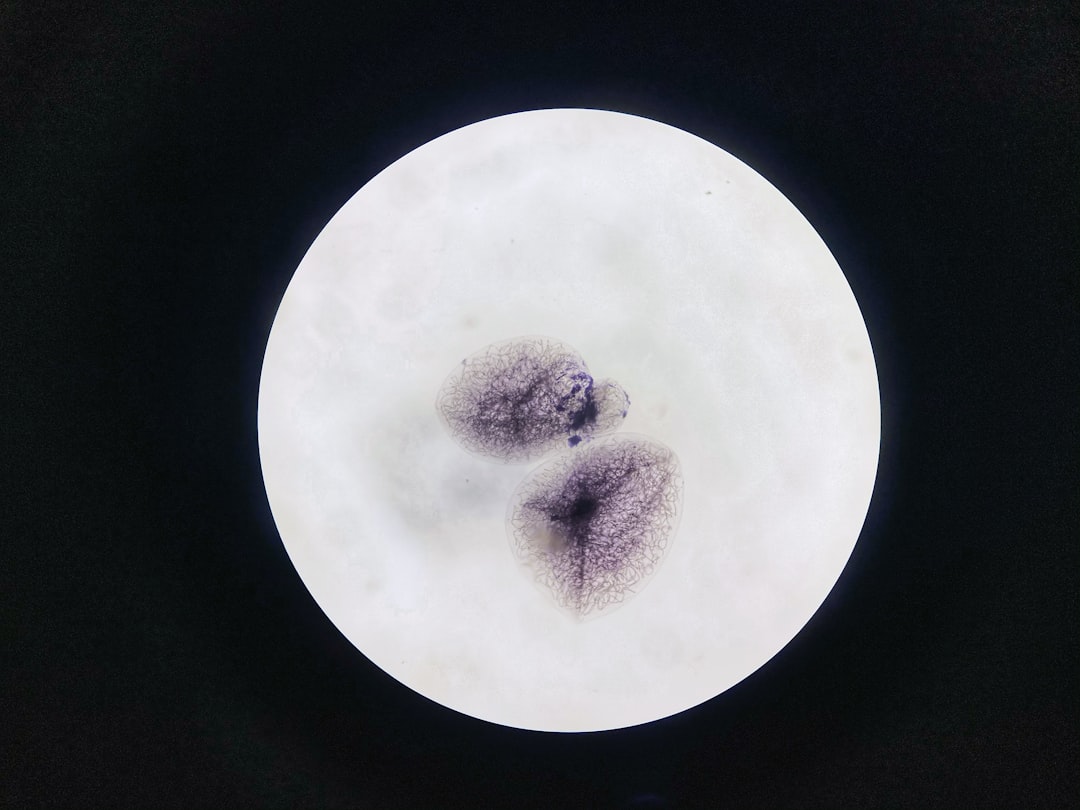

소세포폐암은 소세포폐암이라는 이름에서 알 수 있듯이, 신경 내분비 세포에서 기인하는 일종의 폐암입니다. 일반적으로 다른 유형의 폐암보다 더 빠르게 성장하며 퍼지는 경향이 있습니다. 이 암의 가장 큰 특징은 이미 질병이 상당히 진행된 상태에서 진단이 되는 경우가 많다는 점입니다. 그들은 폭넓은 전이를 포함하여 치료 및 관리가 복잡할 수 있습니다. 이렇게 위험한 암이기에, 조기에 발견하고 적절한 치료를 받는 것이 매우 중요합니다.